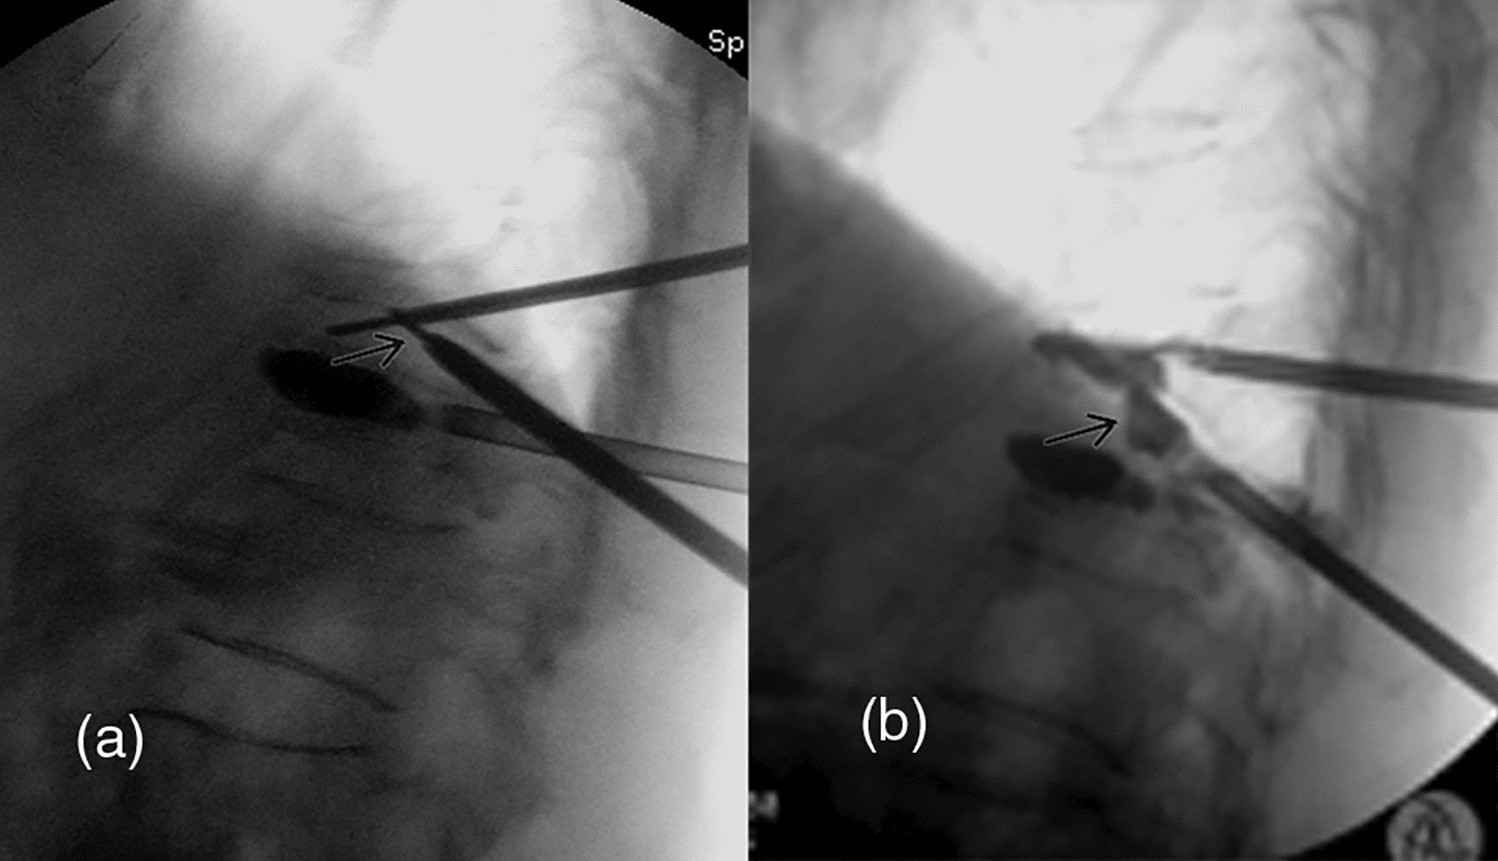

Figure 3

Lateral fluoroscopic images in operation. (a) Intervertebral puncture trajectory connected those in the two adjacent vertebrae (arrow); (b) cement injection from the cranial and caudal trajectory and the intervertebral trajectory (arrow).